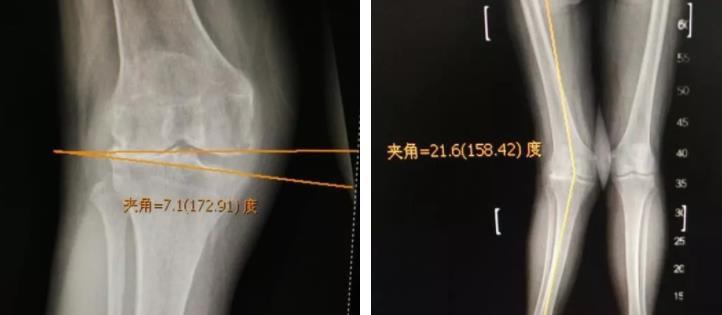

股骨远端截骨矫正膝外翻

图片尺寸1238x949